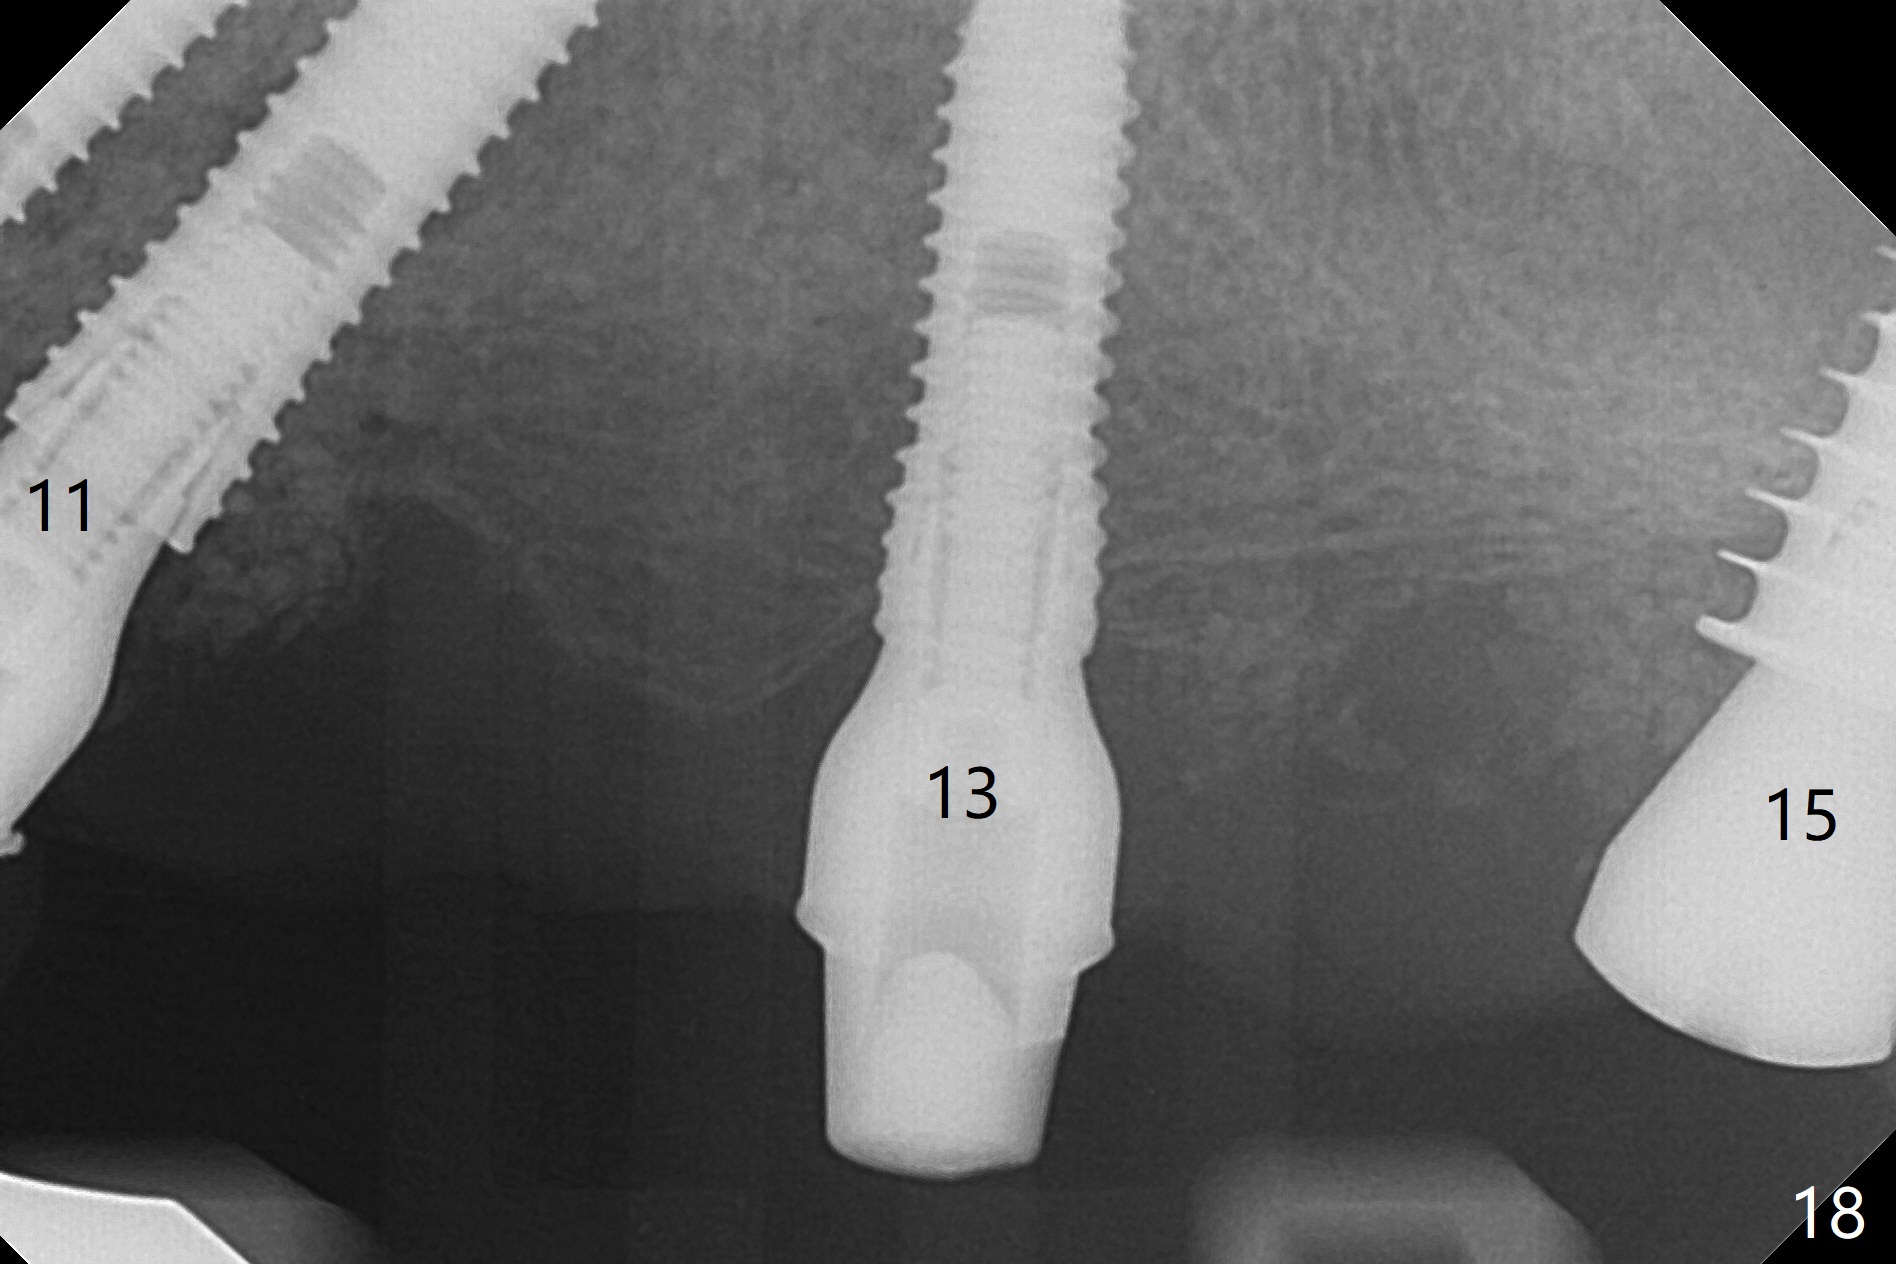

The patient returns 8 days postop, uncomfortable with overhang in the provisional (Fig.10 *). The sockets appear to be healing with loose bone graft (Fig.11) when the provisional is removed for trimming (Fig.12). Six (for #7,13) and seven (#9-11,15) months postop, the soft (Fig.13,17) and hard (Fig.14-16,18) tissues heal. It appears that the trajectory at #9,11 and 13 should be changed by using angled abutments (Fig.18,19 (panoramic X-ray taken 2 months earlier)) before provisional and final restoration.

In fact angled abutments are used at #11 and 13 (4.5x15 degree (5 mm)A) with a straight abutment at #15 (5.5x4(4) mm).